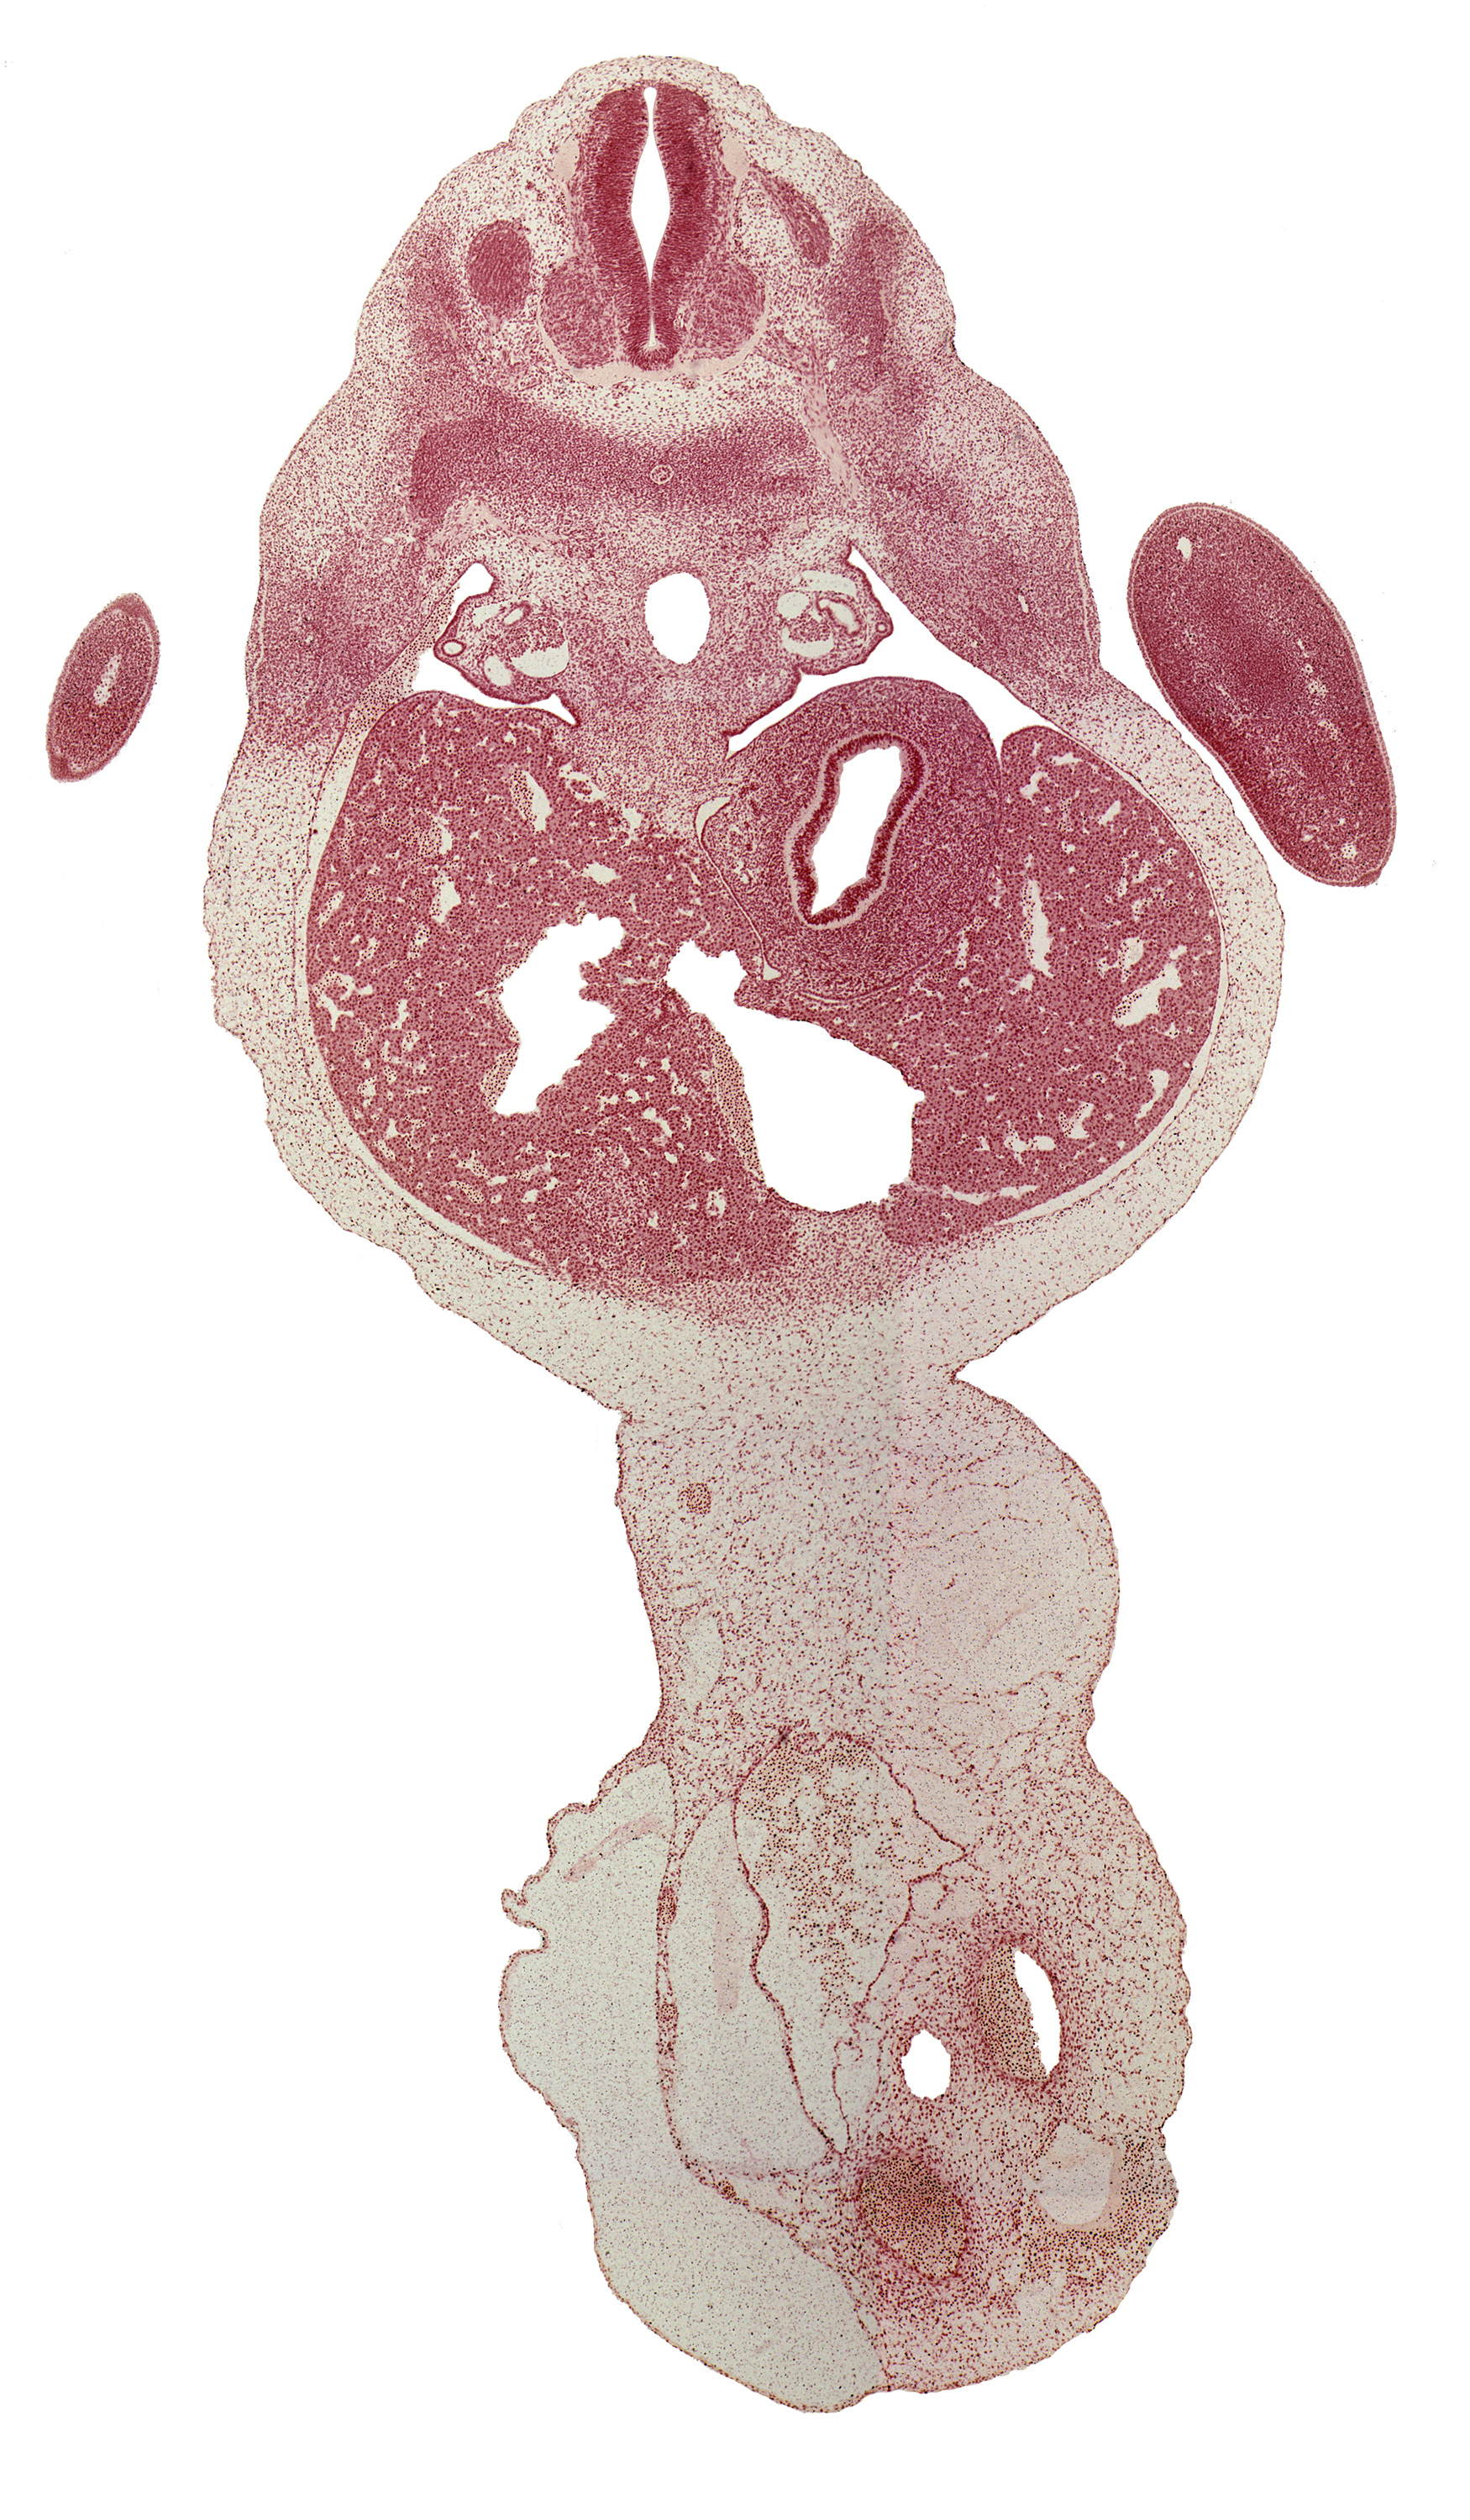

Carnegie Embryo #6517 | Location: 28-04-03

Keywords: T-1 spinal ganglion, T-2 intercostal nerve, T-2 spinal nerve, afferent hepatic vein, aorta, bare area of liver, caudal edge of hand plate, central canal, ductus venosus, left lobe of liver, marginal vein, mesonephric duct, neural arch, peritoneal cavity, right lobe of liver, umbilical cord

Source: The Virtual Human Embryo.